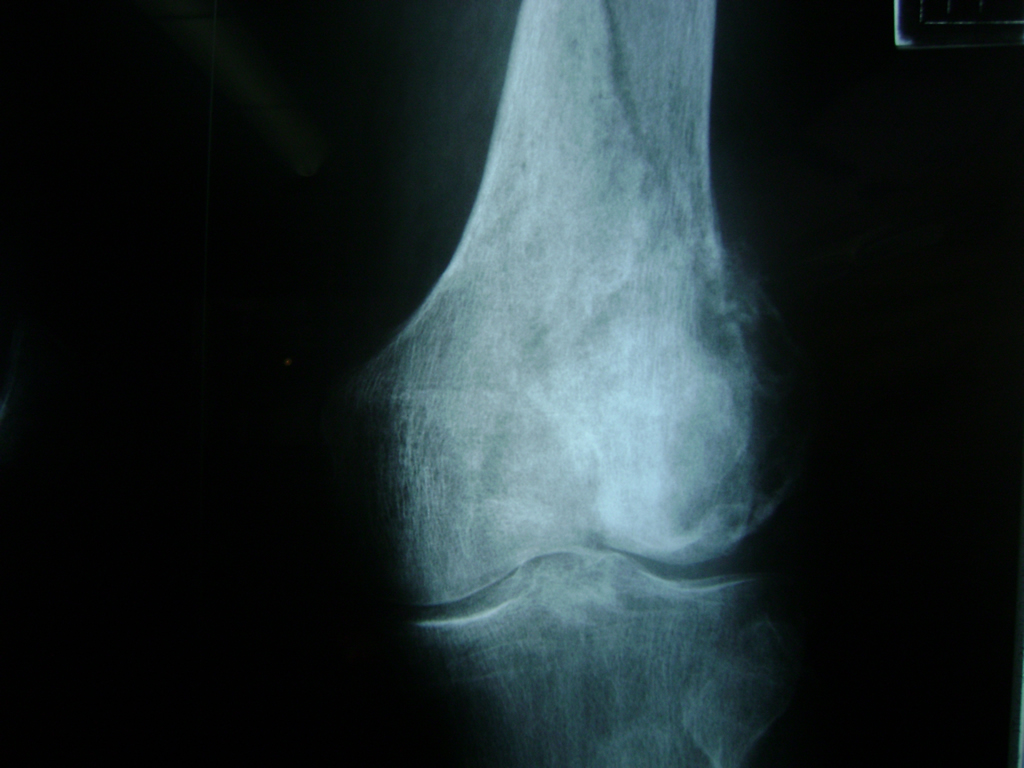

Cirugías de Peroné y Tibia

La artroscopia de rodilla es un cirugía en el cual la estructura interna de la articulación es examinada ya sea para realizar un diagnostico o para realizar un tratamiento, este procedimiento se realiza utilizando un instrumento parecido a un pequeño tubo llamado artroscopio.